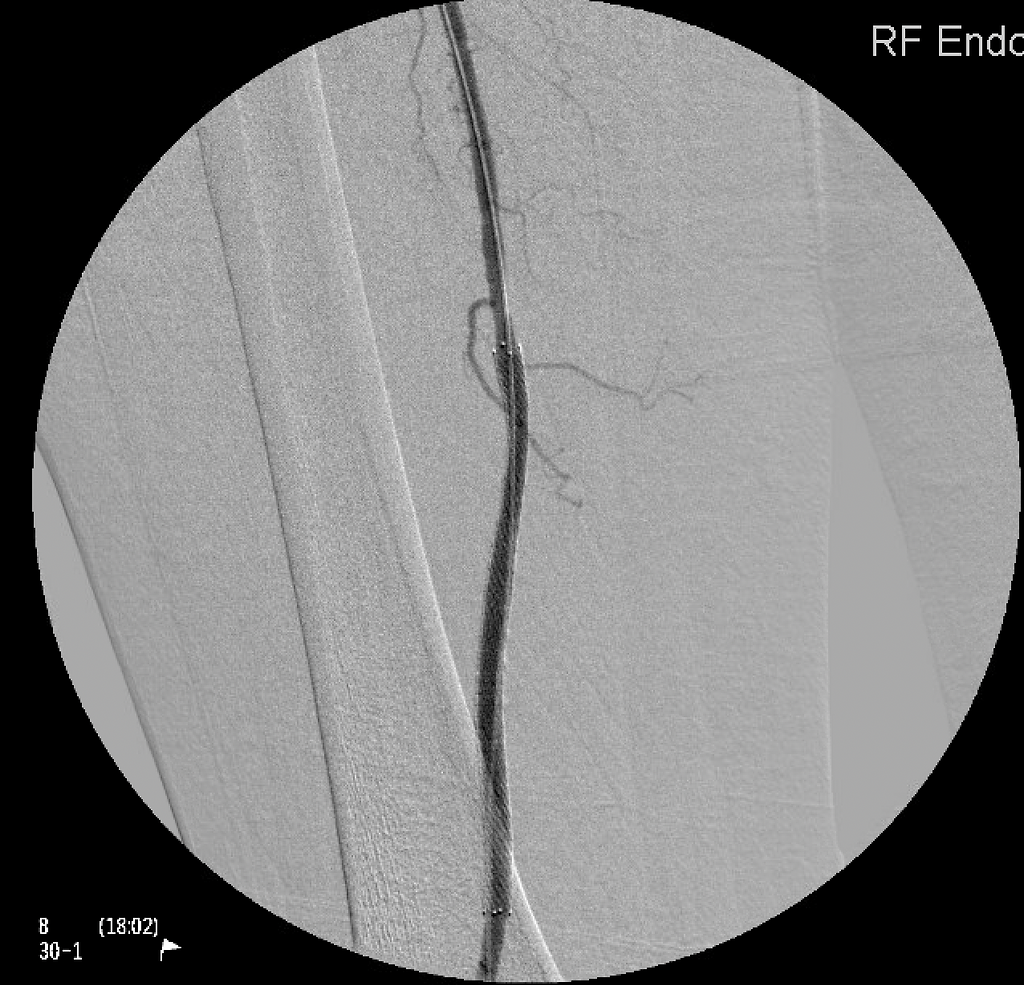

Endovascular treatment for arterial disease utilizes minimally invasive procedures, like angioplasty and stent placement, to restore and support blood flow, providing effective and targeted interventions for improved vascular health.